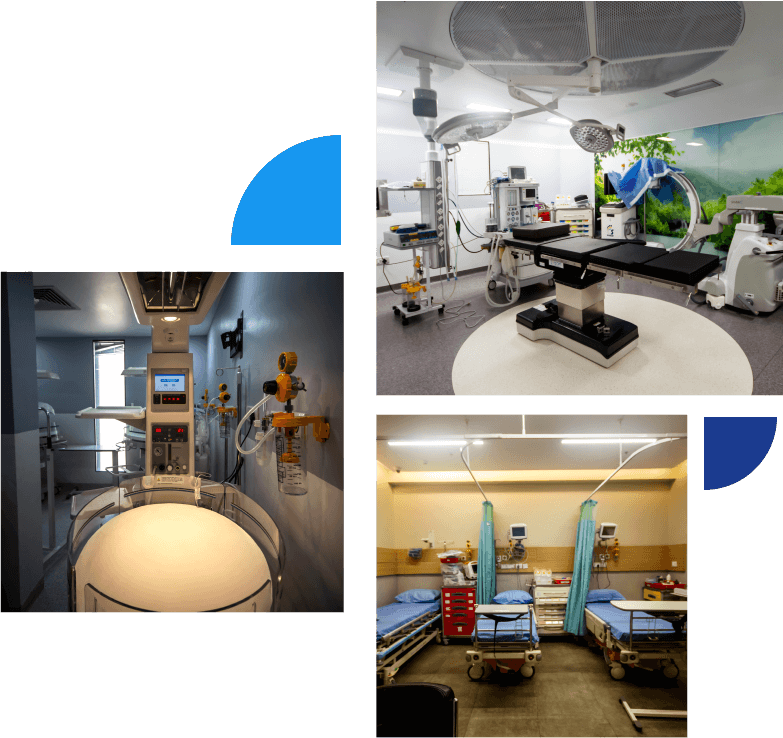

Cura comes with state-of-the-art world class facilities and is a multispecialty hospital situated in the heart of Kanakapura Road and Kammanahalli Bangalore. We at Cura are making the best of the exceptionally talented specialists and the latest equipment to provide you the best of medical facilities to ensure best health for you.

State-of-the-art technology and world-class expertise with the constant support of an extremely friendly administrative and supportive staff, the expert physicians who have degrees from abroad and best universities of India, we strive to give nothing short of best healthcare facilities. We have all kinds of latest technologies and well equipped Orthopedic surgery equipment in terms of recovery areas, operating theaters, and post therapy centers. Our operation theaters are well equipped with top class image intensifiers, top of the line arthroscopy system, computer navigation system, and operating microscope.